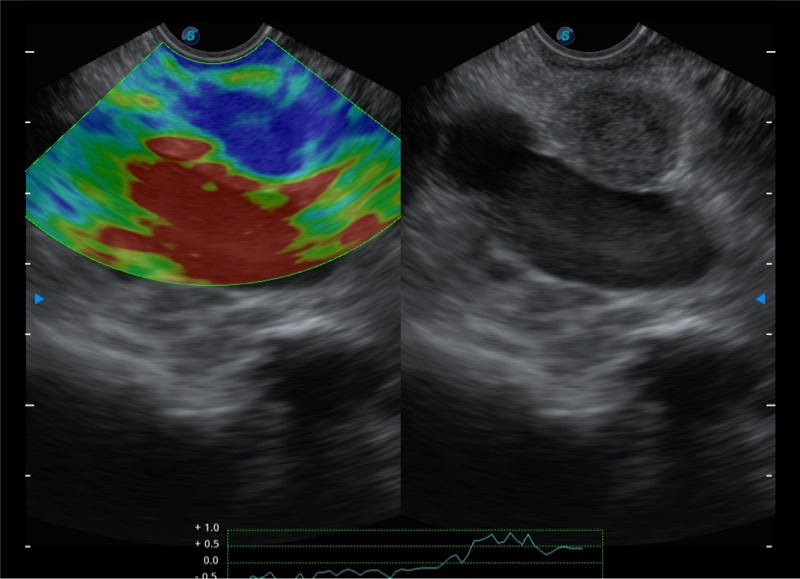

基于二十年的超声技术积累,银河集团官网提供了最新一代的独立超声主机,在提供高质量图像的同时满足多学科使用。具备常见多普勒技术并提供弹性成像、声学造影等高端影像技术。新一代传感器具有更强的抗干扰能力并减少图像伪影。